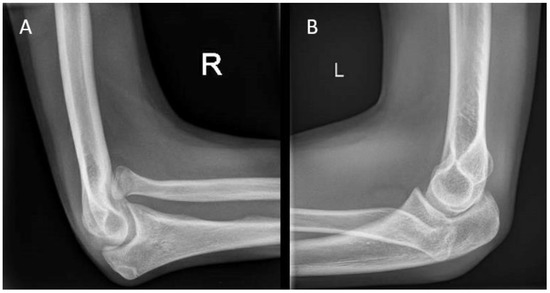

Figure 5. (A) A 17-year-old boy with congenital anterior radial head dislocations of the right arm. (B) A 16-year-old girl with congenital posterior radial head dislocations of the left arm, accompanied by a symptomatic elbow contracture. The girl was treated conservatively with a static progressive elbow flexion brace.

Proximal radial fractures represent up to 10% of all pediatric elbow fractures [29,30]. The mechanism of injury is usually a fall on an outstretched hand, combined with a compressive valgus force across the elbow joint. Despite the occurrence of these fractures around the growth plate, premature physeal closure occurs in about 1.5% of patients [30]. Growth has more impact, however, in congenital radial head dislocations (Figure 5). Although rare in absolute numbers, it is the most common congenital elbow abnormality, accounting for up to 10% [31]. Dislocations occur bilaterally in most cases. Around 70% of dislocations occur posteriorly, followed by anterior and lateral dislocations, occurring around 15% each [31]. With frequent dislocations, the normal anatomical relation of the radial head with the capitellum and the proximal radioulnar joint (PRUJ) during growth may be lost. Without the pressure of the radial head onto the capitellum during growth, a malformation of the radial head with loss of concavity occurs, making reduction in longstanding cases impossible [31]. Patients are generally presented with a painless mass at visual inspection or palpation. Elbow flexion may be slightly decreased in the case of an anterior dislocation, and extension may be slightly decreased in the case of a posterior dislocation. Additionally, DRUJ alignment may be lost, resulting in decreased ROM during pronation and supination [31]. A lateral elbow radiograph is often sufficient to diagnose this condition. Herein, the extent of radial head deformation is a reliable guideline in the decision of whether to operate on a patient [32]. If the radial head is more dome-shaped and has lost all its concavity, surgery tends to be unsuccessful.